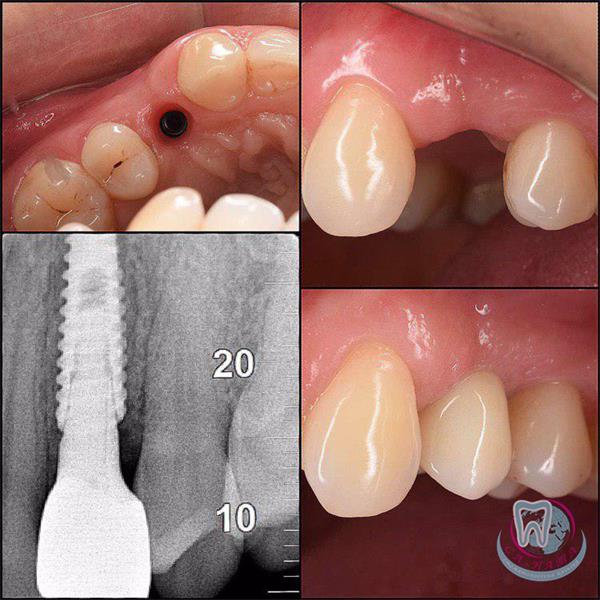

• Installation of the implant. The implant is placed in a pre-prepared bed in the bone of the alveolar outgrowth. After that, the implant (pin) is screwed into the prepared bed and a special plug is installed to protect the implant from tissue growth into it.

• X-ray control. A control X-ray image of the already installed implant is carried out.

• Gingiva former. 2-6 months after the implantation, the implant surgeon proceeds to the next stage – the installation of the former into the gum. To do this, it is necessary to evaluate the engraftment of a previously installed implant using X-ray diagnostics and then proceed with the installation. The shaper is a temporary element of the implantation system, which ensures the formation of the correct hole for the future abutment and the formation of an even, aesthetic gum. To install the former, tissue is excised above the installed implant, the protective plug is removed, and the former itself is installed.

• Making a crown and installing an abutment. At this stage, a 3-D jaw scan is performed, the result of which is sent to the Sa-Nata Dynasty laboratory. Based on the scan result, the dental technician makes an individual prosthetic structure – a crown. The former is worn from 7 to 14 days, then it is replaced with a permanent abutment. An abutment is a connecting element on which the future crown will be attached.

• Installation of the crown. After the individual prosthesis is ready, the specialist installs the crown part, which is attached to the previously installed abutment.